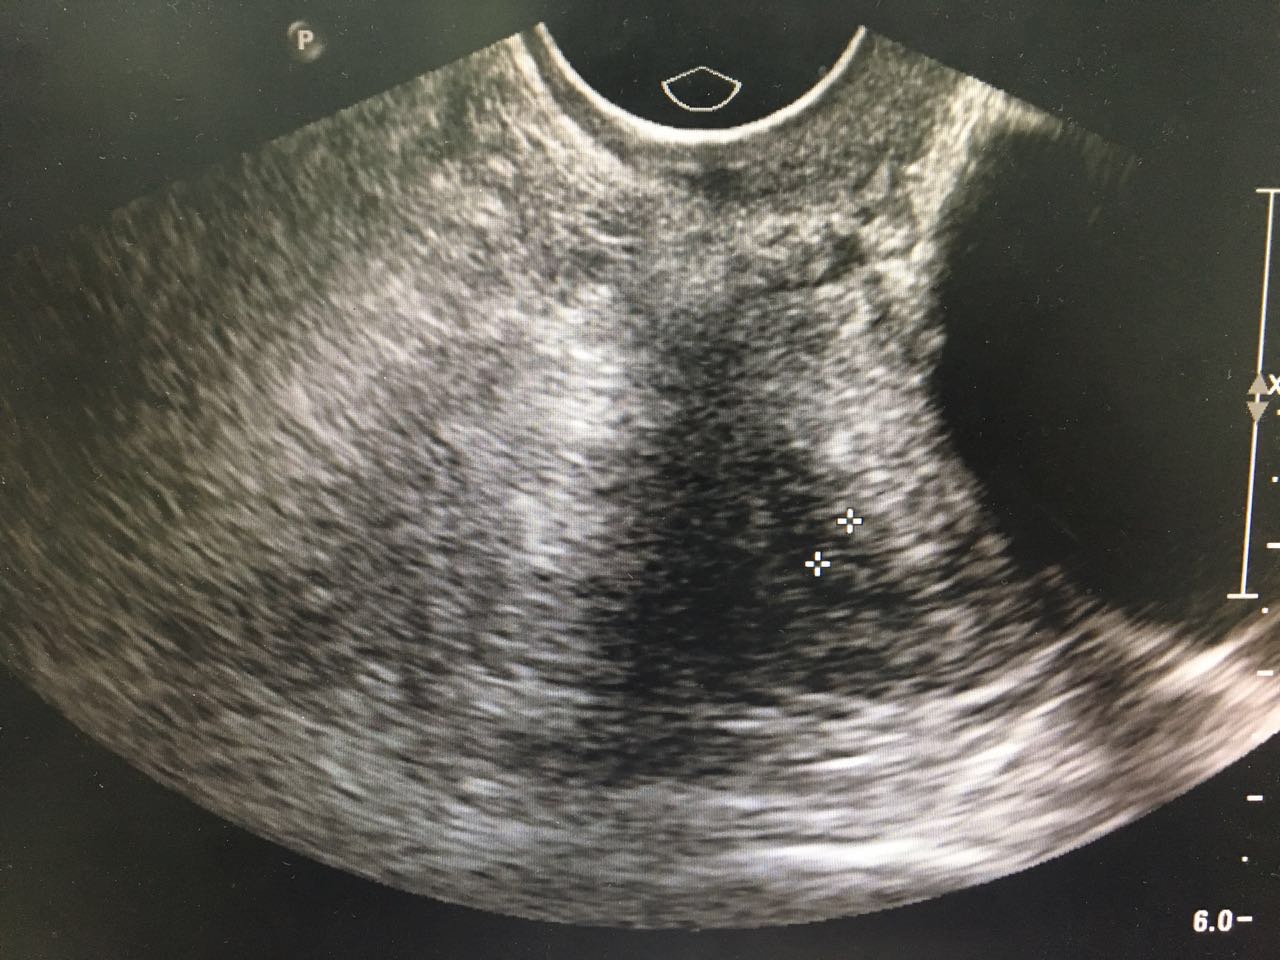

1、 患者女性,58岁  2、 主诉:发现盆腔肿物3月余;  3、 现病史:3-0-0-3,绝经2年。患者2015年体检未见明显异常,3月前体检时发现下腹部有一包块,无腹胀腹痛,无阴道出血,无阴道流液,无尿频尿急。查【妇科超声】示:左附件囊肿,卵巢囊腺瘤可能(子宫后上方无回声区116*94*110,形态规则,边界清晰,内壁光滑,后方回声增强,内见回声隔分隔成两房,隔上未见明显血流信号),【TCT】未见上皮内病变细胞或恶性细胞,肿瘤标志物检查未见异常。后行阴道镜检查示:宫颈转化区II型,宫颈活检病理报告:宫颈3、6、9、12点为黏膜慢性炎。现患者为求进一步诊治,门诊拟“左附件囊肿”收治入院。 自发病以来,患者精神可,一般情况可,睡眠可,胃纳可,二便基本正常。

4、妇科体检: 外阴(-);阴道畅;宫颈光,局部宫颈活检后改变;宫体:前位,偏向左侧,萎缩,表面光滑,活动可;子宫左上方可及囊性肿块直径8cm左右,质软,活动尚可,无压痛,右附件区未及明显异常。  5、辅助检查: 生化、血常规、阴道分泌物、内分泌检查未见异常 【TCT】:未见上皮内病变细胞或恶性细胞